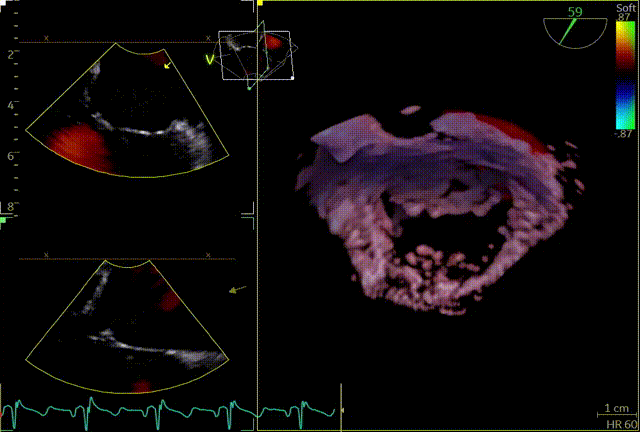

术前心超团队王蓓教授以及余婵教授对患者的瓣膜解剖情况进行了详细的评估:

① 二尖瓣后叶广泛栓系,前后叶对合不良,二尖瓣重度关闭不全,Carpentier分型Ⅲb,反流程度4+;

② 画迹法显示二尖瓣瓣口面积5.25cm²,平均跨瓣压差4.2mmHg;

③ 二尖瓣前叶(A1)长度28.5mm,二尖瓣后叶(P1)长度: 10.4mm;二尖瓣前叶(A2)长度28.4mm,二尖瓣后叶(P2)长度: 12.7mm二尖瓣前叶(A3)长度22.6mm,二尖瓣后叶(P3)长度: 11.5mm;

④ 3区前后叶对合gap 4.5mm,2区前后叶对合gap 3mm。

3D

3D带彩